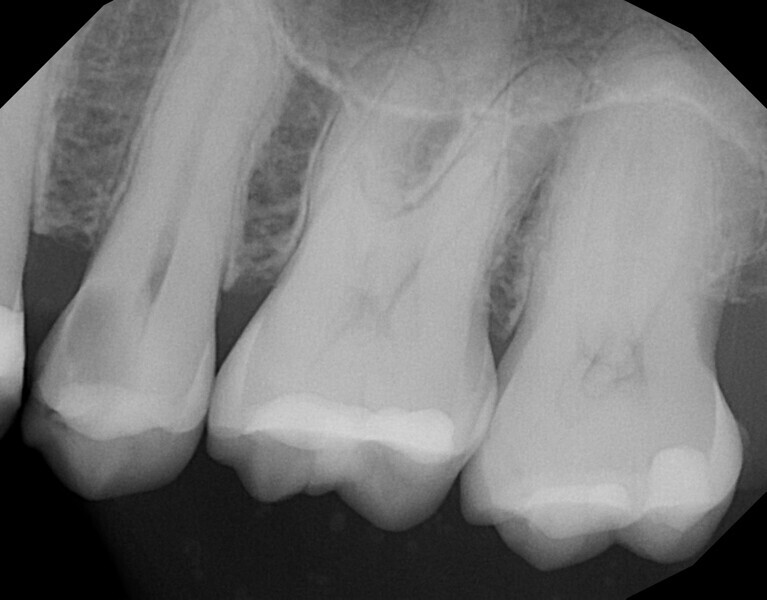

A 34-year-old female patient presented with the complaint of pain and temperature sensitivity in the maxillary right posterior. Clinical examination noted caries on the distal aspect of the second molar, and a periapical radiograph was taken (Fig. 10). Deep caries was confirmed radiographically on the disto-occlusal aspect of tooth #17 that was very close to the pulp, but a lack of periapical pathology was noted. The tooth was tested with cold to verify that the pulp was vital. A mild reaction was noted when cold was applied that immediately resolved when cold was removed from the tooth, indicating that the tooth was vital. The patient was informed that pulpal exposure would most likely result from caries removal and endodontic treatment may thus be necessary or become necessary at a later date after treatment. Treatment would consist of laser pulpal treatment should a large exposure not result, followed by a core build-up and restoration with a complete crown. The patient agreed to the recommended treatment.

The patient was seen at routine prophylactic recall appointments, and at the five-year recall appointment, a periapical radiograph was taken (Fig. 12). As was noted in prior follow-up radiographs, no periapical radiolucency was seen, demonstrating that the laser treatment had been successful in preventing periapical pathology and pulpal infection.

Fig. 10: Periapical radiograph taken preoperatively, demonstrating deep caries on the disto-occlusal aspect and minimal tooth substance over the pulp.

Fig. 12: Periapical radiograph five years after laser pulpal treatment and restoration of the tooth, demonstrating no periapical pathology.